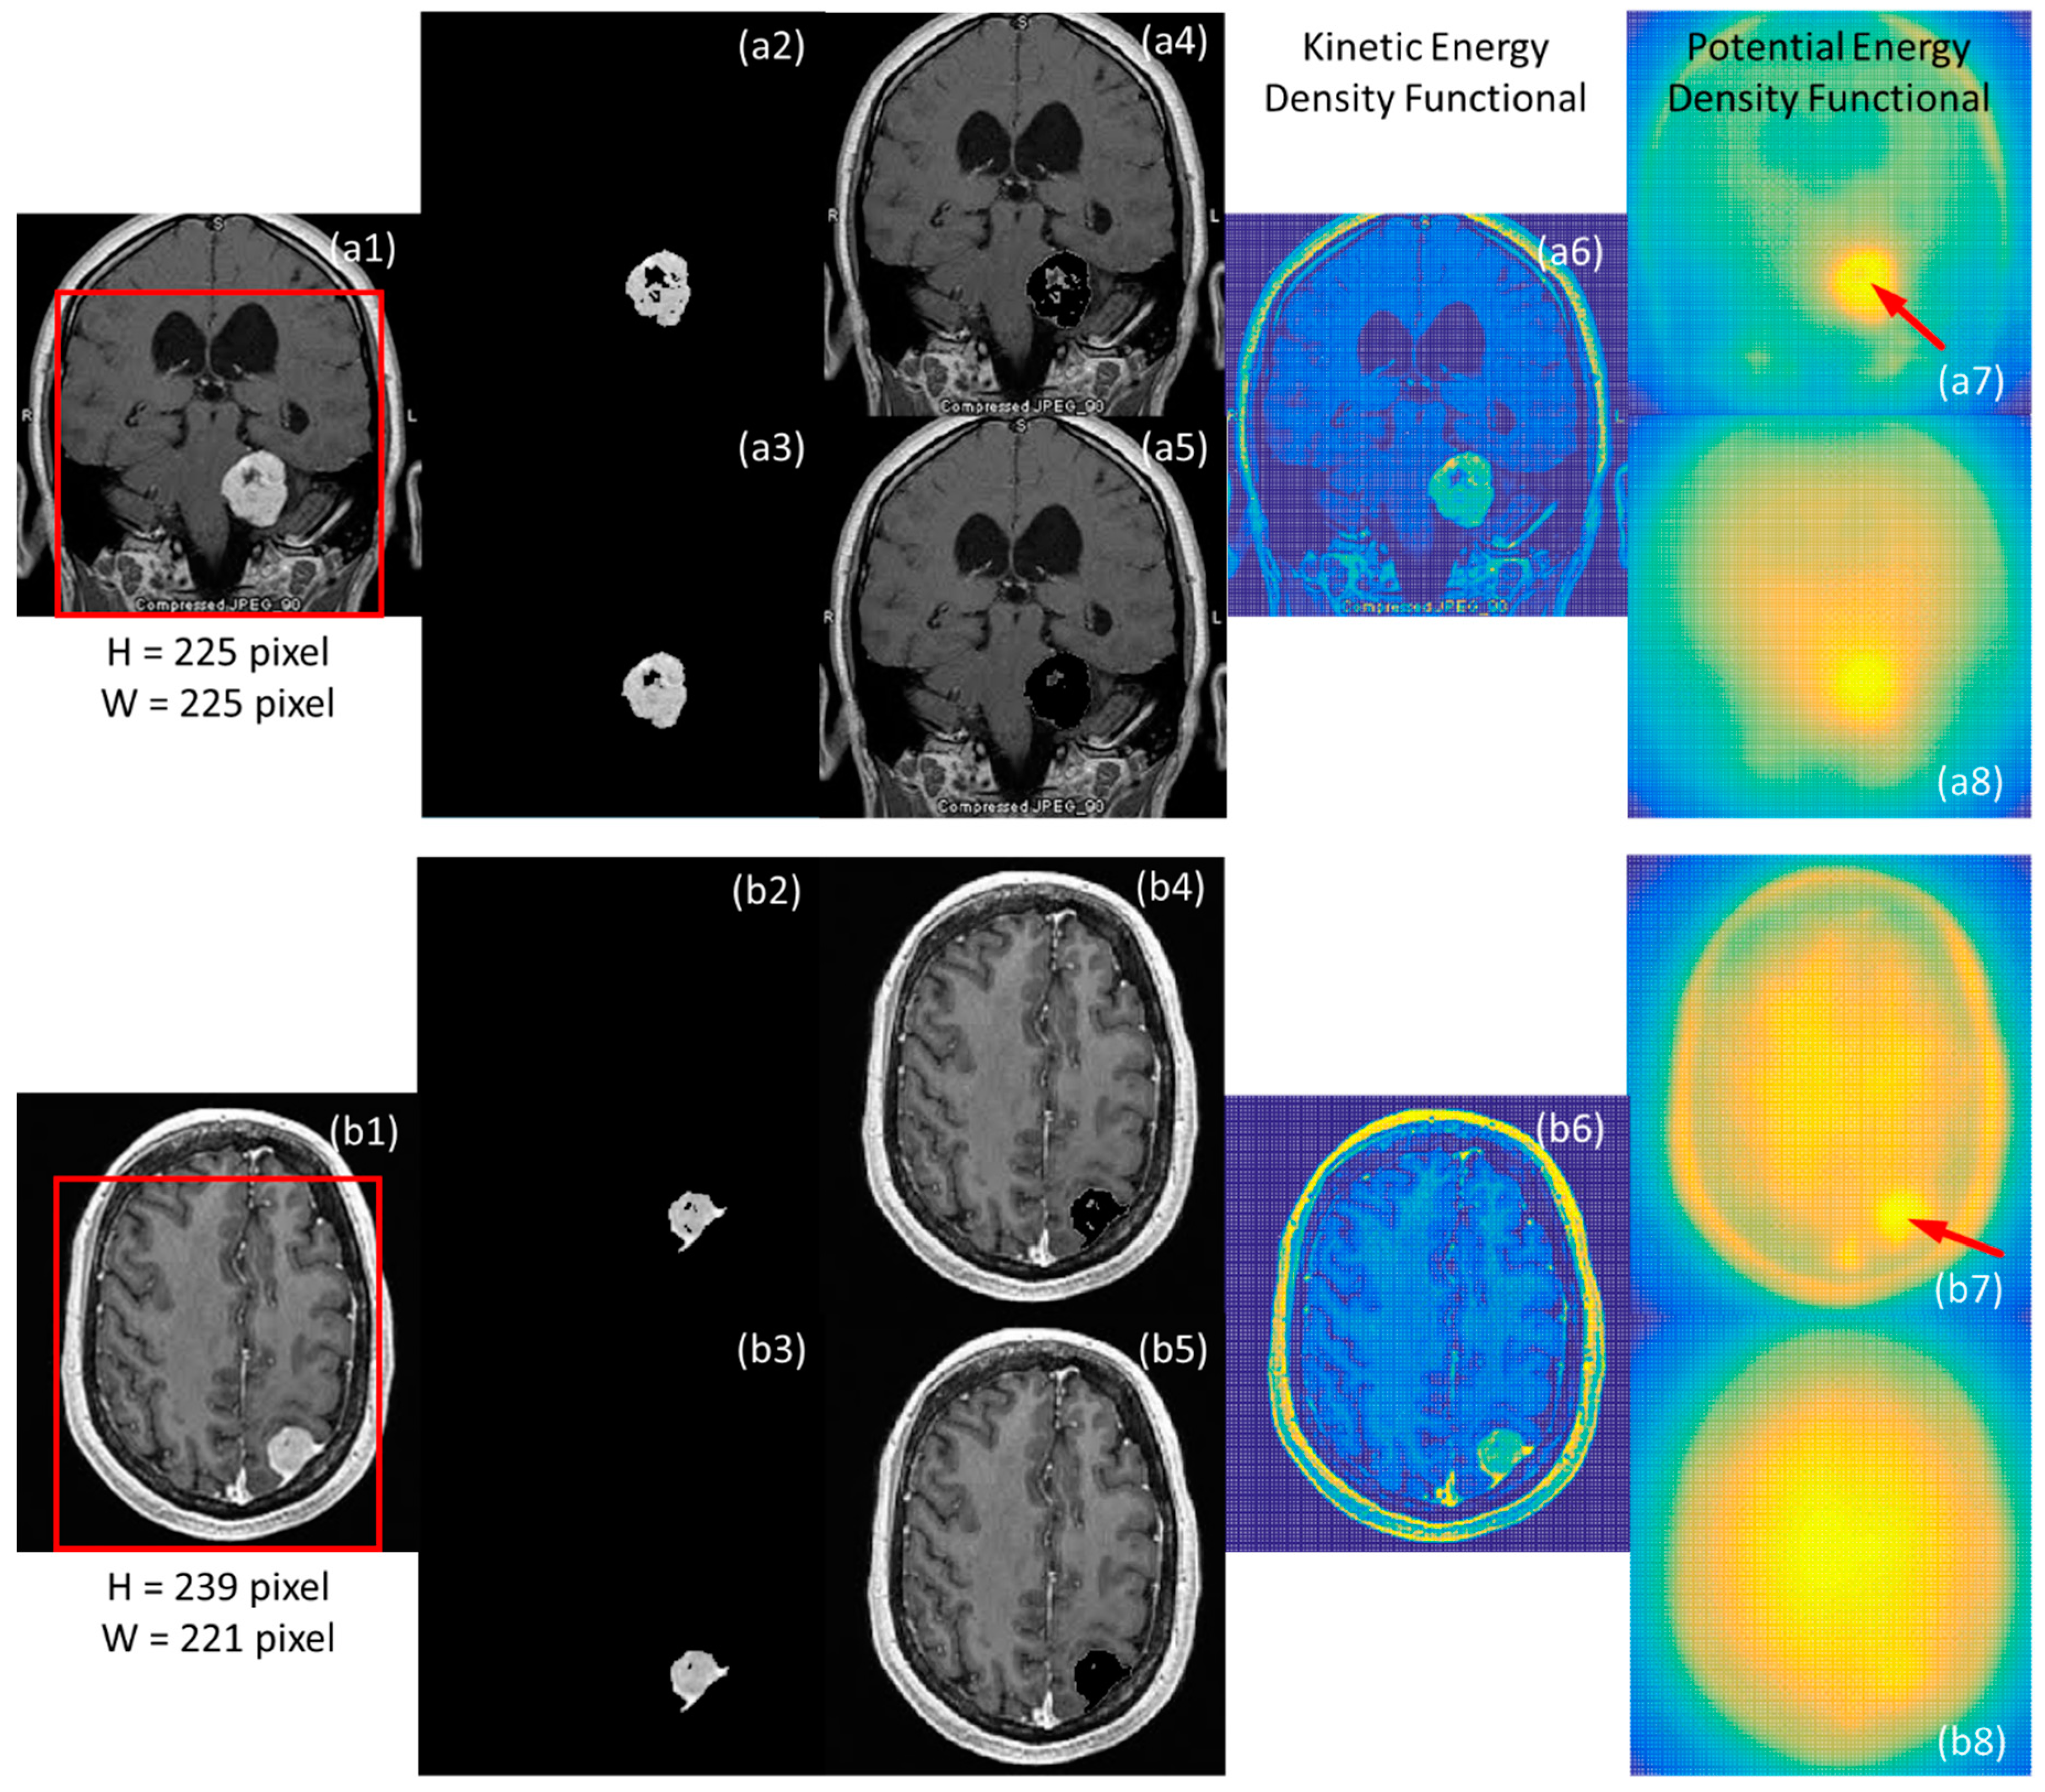

Figure 1 illustrates the results of image segmentation utilizing various potential kernels and sharpened kinetic energy density functionals. The original MR images are illustrated in Figure 1(a1,b1), respectively, and regions of interest (ROI) are also indicated in both original images using red rectangular windows. The size of each window was set to be 80% length and width of each image to avoid catching undesired featured components from skulls. The segmentation results, shown in Figure 1(a2,a4,b2,b4), were obtained using the simple potential kernel in Equation (2), while those shown in Figure 1(a3,a5,b3,b5) were obtained using the square-root potential kernel in Equation (6). Morphologies of kinetic energy density functional of employed original MR images are, respectively, illustrated in Figure 1(a6,b6). Then, morphologies of potential energy density functionals with the simple potential kernel are, respectively, shown in Figure 1(a7,b7), while those with the square-root potential kernel are, respectively, shown in Figure 1(a8,b8). From the profiles of the potential energy density functionals, it is obvious that the smooth performance of using the square-root potential kernel was better than that of the simple potential kernel. For instance, the spot indicated by the red arrow inserted in Figure 1(a7) became smooth when replacing the simple kernel using the square-root potential kernel, and the result is shown in Figure 1(a8). Thus, the segmentation result was also smoothened, as shown in Figure 1(a3). By comparing Figure 1(a2,a3), the fragmentary parts of the segmentation result using the simple kernel was mended by means of the square-root kernel. Similarly, the high energy part indicated by the red arrow shown in Figure 1(b7) was smoothened by taking the square-root kernel, and the smoothing segmentation result is shown in Figure 1(b3). It is noted that, in the tentative experiments, the segmentation consequences using the Yukawa potential kernel did not exhibit obvious benefits compared to the simple one in the employed MR images.

Figure 1.

Two original MR images, as shown in (a1,b1), sourced from Ref. [62] were employed to study performances of those utilized potential kernels. Regions of interest in each MR image were defined to avoid undesired segmentation results from skulls by red rectangular windows. According to the estimated morphologies of energy density functionals, shown in the late two columns, the segmentation results were obtained using the proposed framework and are as illustrated in second and third columns, as respectively shown from (a2) to (a5) and from (b2) to (b5). It is noted that the potential kernel used in (a7) and (b7) was the simple potential kernel, while that used in (a8) and (b8) was the square-root potential kernel.